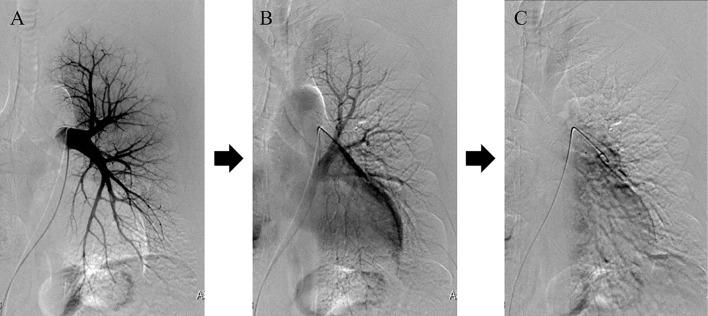

We herein report a 48-year-old man with a history of chronic atrial fibrillation (AF) and repeated hemoptysis after radiofrequency ablation. Contrast tomography showed soft tissue thickening of the left hilar region and left pulmonary vein stenosis. We performed bronchial artery embolization, but the hemoptysis did not disappear, and AF was not controlled. We performed left lung lobectomy and maze procedures since we considered surgical removal necessary as radical treatment. After the surgery, hemoptysis and atrial fibrillation did not recur. Refractory hemoptysis after catheter ablation is rare, but occasionally occurs in patients with severe pulmonary vein stenosis.

我们在此报告一例 48 岁男性,患有慢性心房颤动(AF)病史,射频消融术后反复咯血。对比断层扫描显示左肺门区软组织增厚,左肺静脉狭窄。我们进行了支气管动脉栓塞,但咯血并未消失,AF 也未得到控制。我们考虑到作为根治性治疗有必要进行手术切除,因此进行了左肺叶切除术和迷宫手术。手术后,咯血和心房颤动均未再复发。射频消融术后难治性咯血较为罕见,但在严重肺静脉狭窄患者中偶有发生。